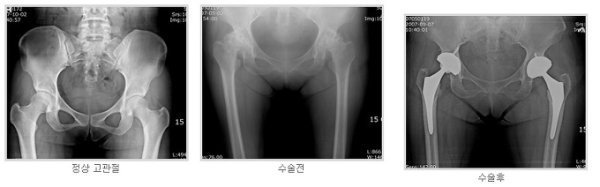

고관절치환술